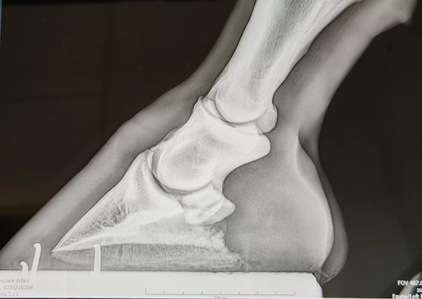

下午4:30--6:00在马医院彭老师对员工进行了X光拍照实操指导,讲解拍摄不同部位时设备不同角度的摆放位置。员工表示之前对X光很陌生,现在接触下来,感觉很新奇,想要进一步探索,彭老师也给员工讲解国外马术俱乐部的工种,鼓励大家多学习理论知识,继而投入到马术行业中来。

讲解蹄部X光拍摄角度

指导X光拍摄并发现马匹跛行原因